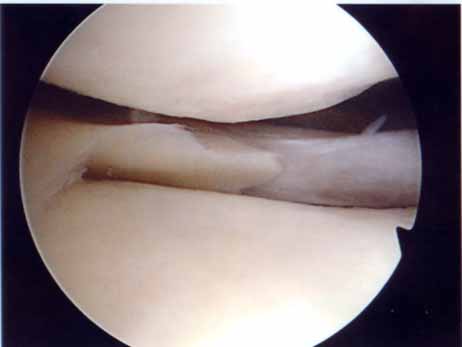

外側円板状半月損傷

外側円板状半月損傷は水平断裂で始まり、強い症状に発展したときは複合断裂になっていることが多くなります。長期経過例では変形性変化を合併することが多くなります(Okazaki 2006)。このタイプの半月板は切れ始めたら正常にできるだけ近い半月板に形成します。手術は関節鏡手術で手術翌日に松葉杖なしで退院出来ます。

完全型円板状半月遊離縁

右:円板状半月